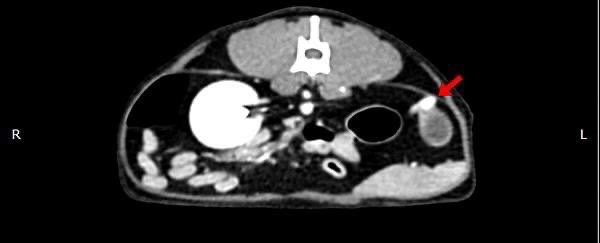

貓咪 卵巢殘留

在他院絕育後仍有發情現象,轉院至築心,經由電腦斷層掃描確認後手術。